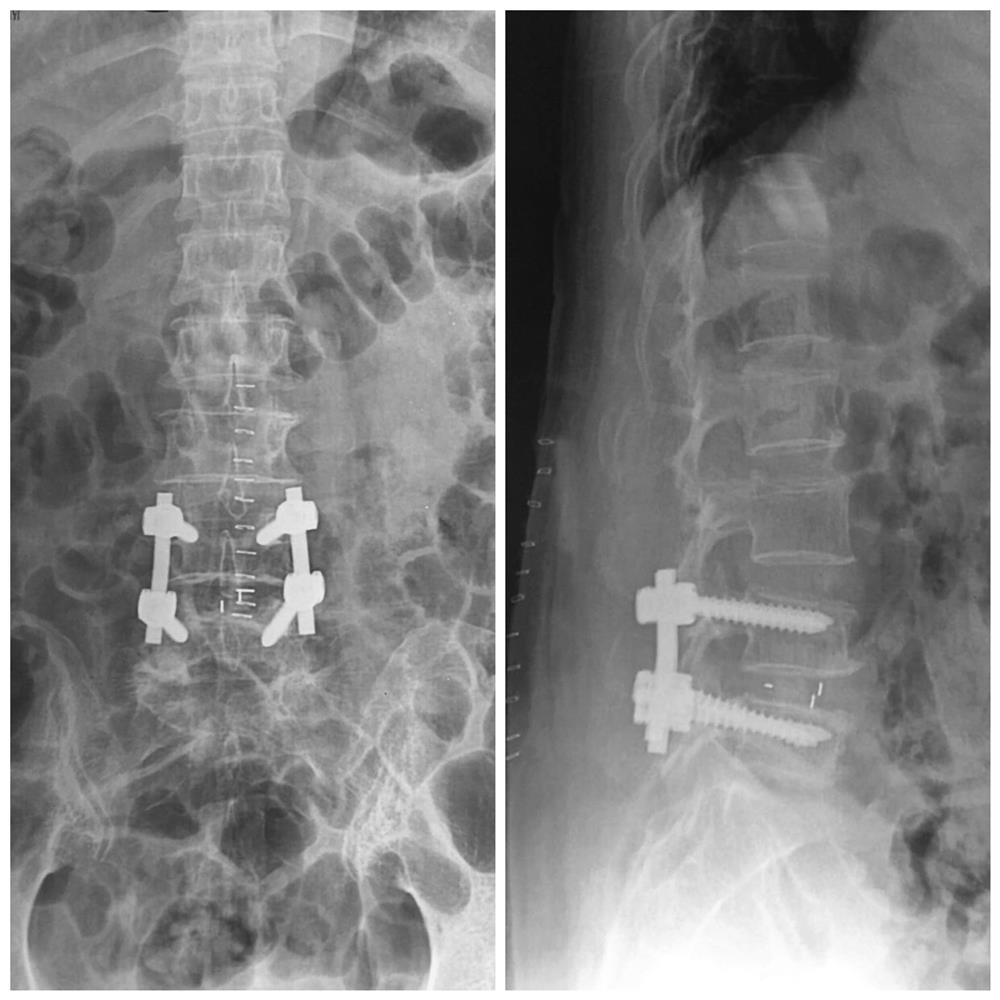

🎁Nhân một trường hợp bệnh nhân nữ 65 tuổi vào viện vì đau nhiều vùng cột sống thắt lưng, đau lan xuống đùi và cẳng chân bên trái, đi lại khó khăn và chỉ đi được vài mét bệnh nhân đã thấy đau tăng lên phải ngồi nghỉ.

Bệnh nhân đã được mở mảnh bên lấy khối thoát đĩa đệm làm vững cột sống bằng nẹp vis L4L5, sau khi mổ xong bệnh nhân hết đau lan xuống mông và chân chỉ còn đau tại vết mổ. Sau mổ 3 ngày bệnh nhân ngồi dậy tập đi lại sau 10 ngày bệnh nhân được cắt chỉ và ra viện!